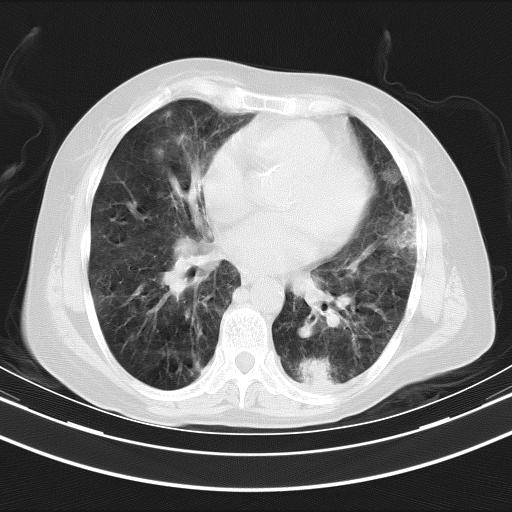

老年女性,嗜睡3天,意识模糊。轻咳,无发热。

双肺多发淡片影,毛玻璃影,,支持支气管肺炎,,建议血气找原因,,嗜睡是否肺性脑病?有没有慢支病史?

双肺炎症,建议抗炎治疗后复查,见过几个老年肺炎病例,没有发烧、咳嗽症状,直接以昏迷就诊。

1)两肺感染性病变;建议抗炎治疗后复查。2)纵隔淋巴结肿大。3)左侧胸腔积液。